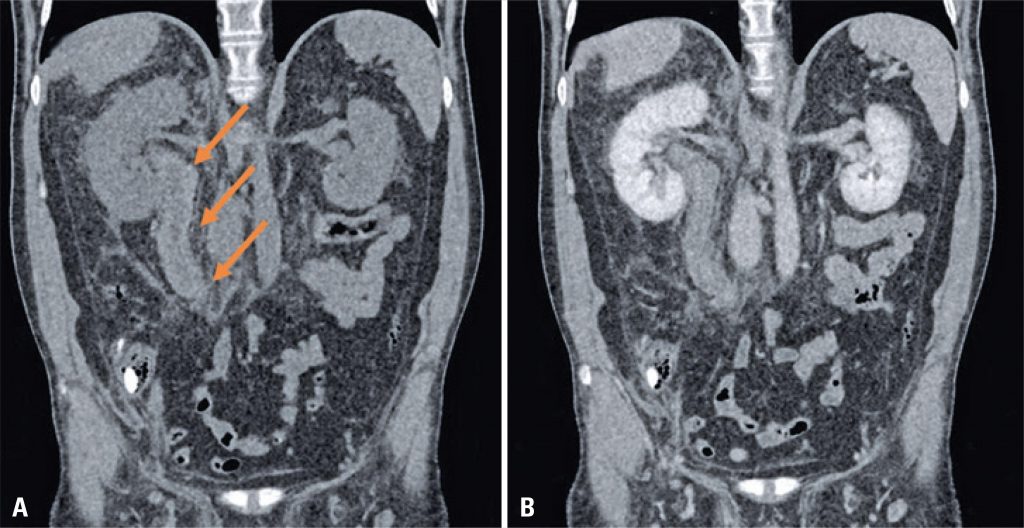

Homem, 55 anos, admitido em serviço de emergência relatando dor aguda no flanco direito. O paciente também se queixava de epitaxe, sangramento gengival e hematúria ao longo dos últimos 3 dias. O exame físico demonstrou hematoma subcutâneo no abdome, com dor à palpação. Sete dias antes desses sintomas, sua dose diária de varfarina fora aumentada. O exame sanguíneo mostrou que a Razão Normalizada Internacional estava marcadamente elevada (3,6; o exame prévio, anterior ao aumento da dosagem, mostrou o índice de 2,2).

Foi solicitada tomografia computadorizada abdominal (), que expôs hiperatenuação e espessamento circunferencial da parede do ureter direito na fase sem contraste, compatível com hematoma expansivo parietal.